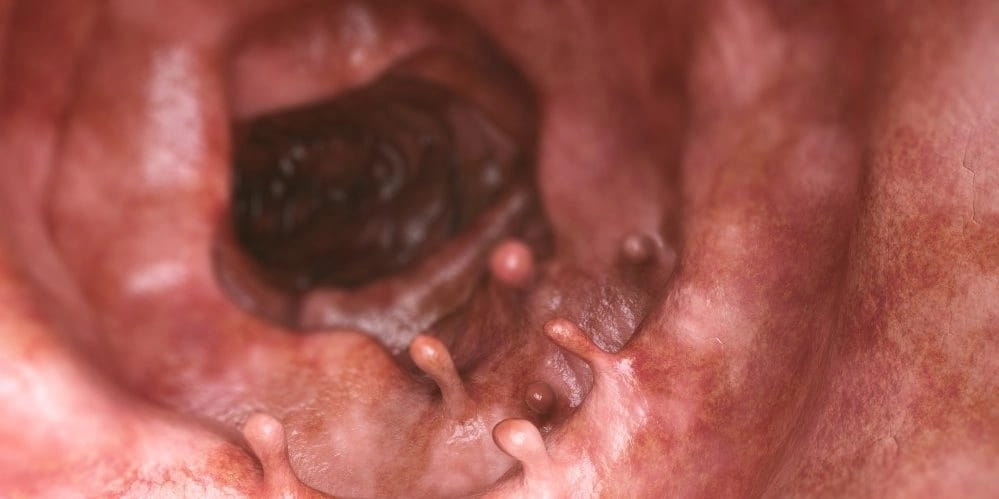

- Одиночный полип, аномальное разрастание тканей. Рост доброкачественных образований приводит к трансформации их в злокачественные.

- Полипы;

Ещё к группе риска относятся те, у кого есть наследственное заболевание – семейный полипоз. Ведь злокачественная опухоль может развиться и из полипа. Если у кого-то из родных заболевание было, нелишним будет обратиться к врачу и пройти плановое обследование.

Прежде всего узкий специалист-онколог проведёт пальцевое исследование прямой кишки. Это исключит геморрой и наличие полипов. Дальше он сам будет выстраивать методику обследования и лечения. Чаще, чтобы подтвердить диагноз, назначают обычное для таких заболеваний обследование – ректоскопию и колоноскопию.